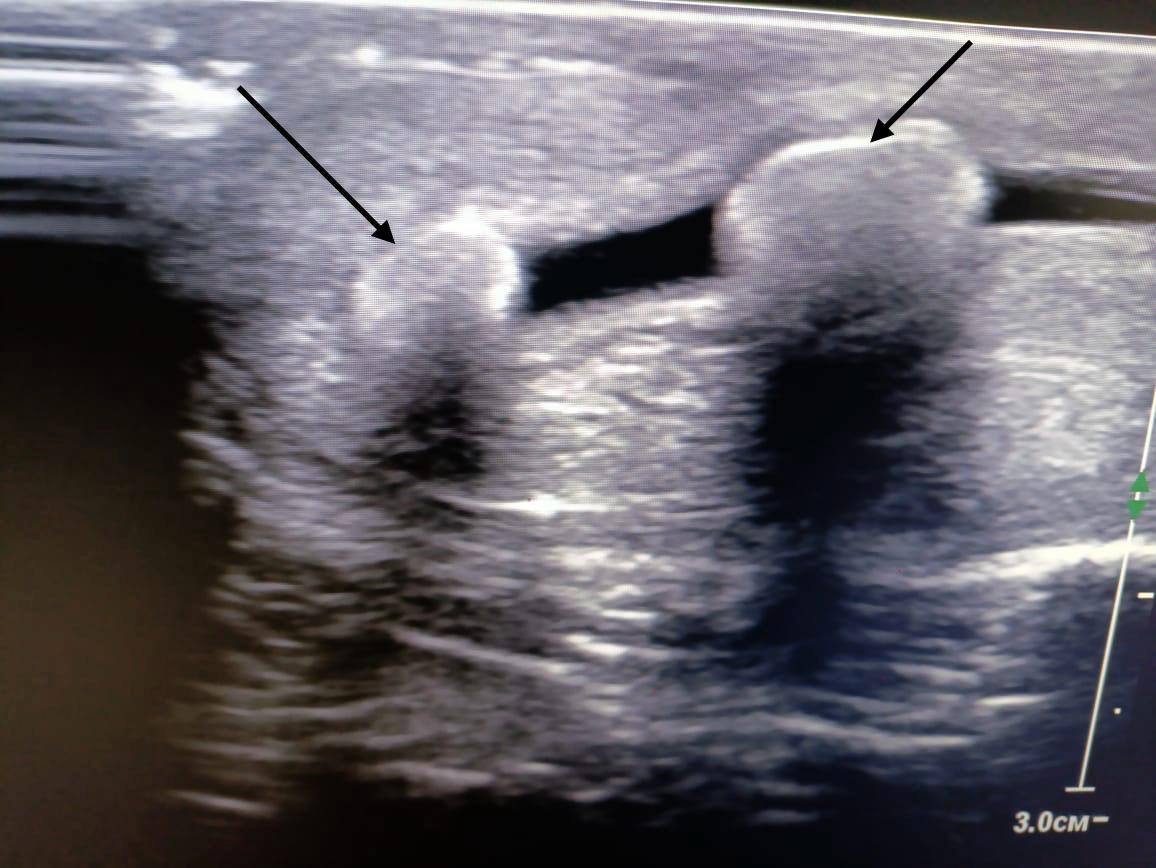

Вот с такими камнями в уретре мучился мужчина из Ставрополя

Пациент обратился к урологу с жалобами на боли и затруднённое мочеиспускание. Мужчину направили на УЗИ, где врачи увидели два огромных камня в уретре. В тот же день камни были извлечены.